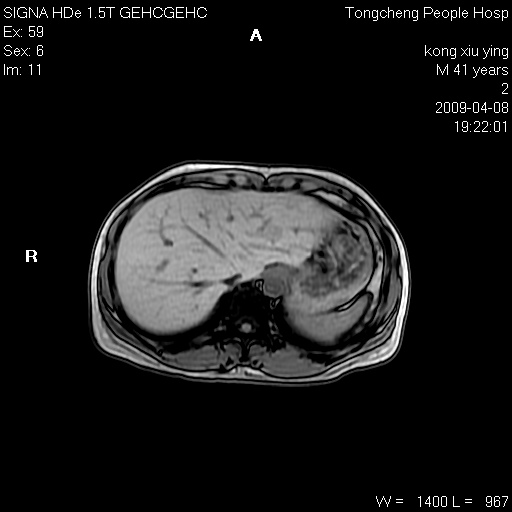

标题: CL1008:【经典】胆囊石榴籽样结石。

女,41岁。健康体检——彩超提示:胆囊显示不清。平素健康,无不适感。

腹部mr扫描及mrcp,图像如下: